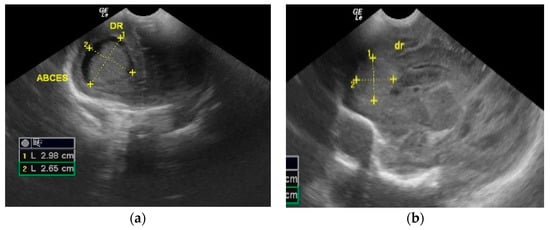

2. Case Presentation